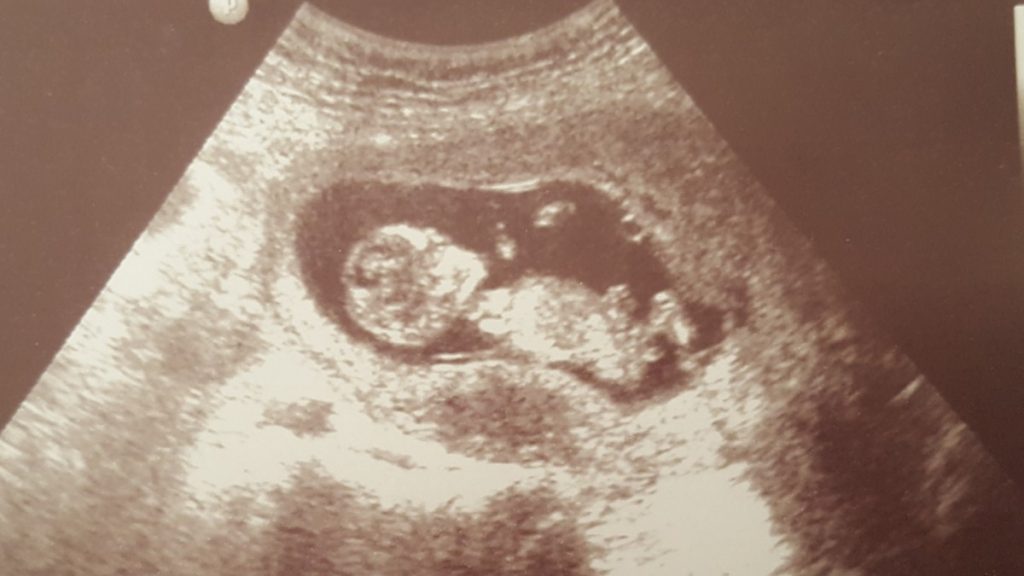

Ondertussen ben ik bijna 17 weken onderweg en voel ik me eindelijk beter. Ruim 10 weken behoorlijk misselijk en vooral moe zijn hakt er wel in. Maar sinds vorige week smaakt het eten weer gewoon en heb ik ook het gevoel dat ik weer mezelf ben. Vandaag zelfs voor het eerst weer 5 kilometer gewandeld. Onbegrijpelijk dat zo’n klein frummeltje ervoor kan zorgen dat je conditie helemaal weg is. Ik moest al minutenlang uit hijgen als ik de trap op was gelopen.Read More